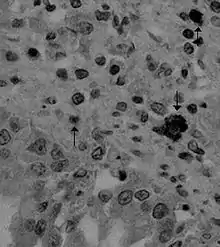

کروناویروس سگسانان (نام علمی: Canine coronavirus) نام یک گونه ویروس از خانواده کروناویریده است. این ویروس از نوع آرانای ویروس تک رشته ای است و موجب عفونت های روده ای بسیار واگیردار در سگ سانان می شود.